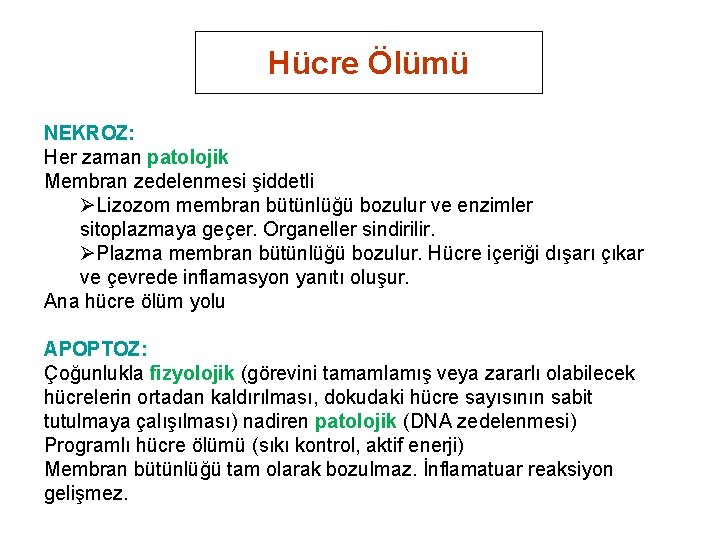

Hücre Ölümü NEKROZ: Her zaman patolojik Membran zedelenmesi şiddetli ØLizozom membran bütünlüğü bozulur ve enzimler sitoplazmaya geçer. Organeller sindirilir. ØPlazma membran bütünlüğü bozulur. Hücre içeriği dışarı çıkar ve çevrede inflamasyon yanıtı oluşur. Ana hücre ölüm yolu APOPTOZ: Çoğunlukla fizyolojik (görevini tamamlamış veya zararlı olabilecek hücrelerin ortadan kaldırılması, dokudaki hücre sayısının sabit tutulmaya çalışılması) nadiren patolojik (DNA zedelenmesi) Programlı hücre ölümü (sıkı kontrol, aktif enerji) Membran bütünlüğü tam olarak bozulmaz. İnflamatuar reaksiyon gelişmez.